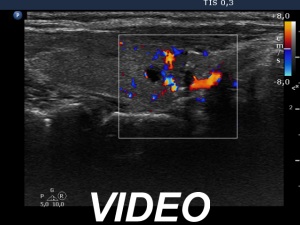

Ultrasonography: The right and the left lobe remained unchanged except for the appearance of a moderately hypoechogenic lesion in the lower, isthmic part of the right lobe. This lesion contained various hyperechogenic granules and was avascular on Doppler mode. The ultrasound presentation stood for a granulation around surgical thread.

The lesion which has appeared on post operative ultrasound might be a regenerative tissue or a granulation around surgical thread. The latter is more likely because the former usually disappears within 4 months after the operation.